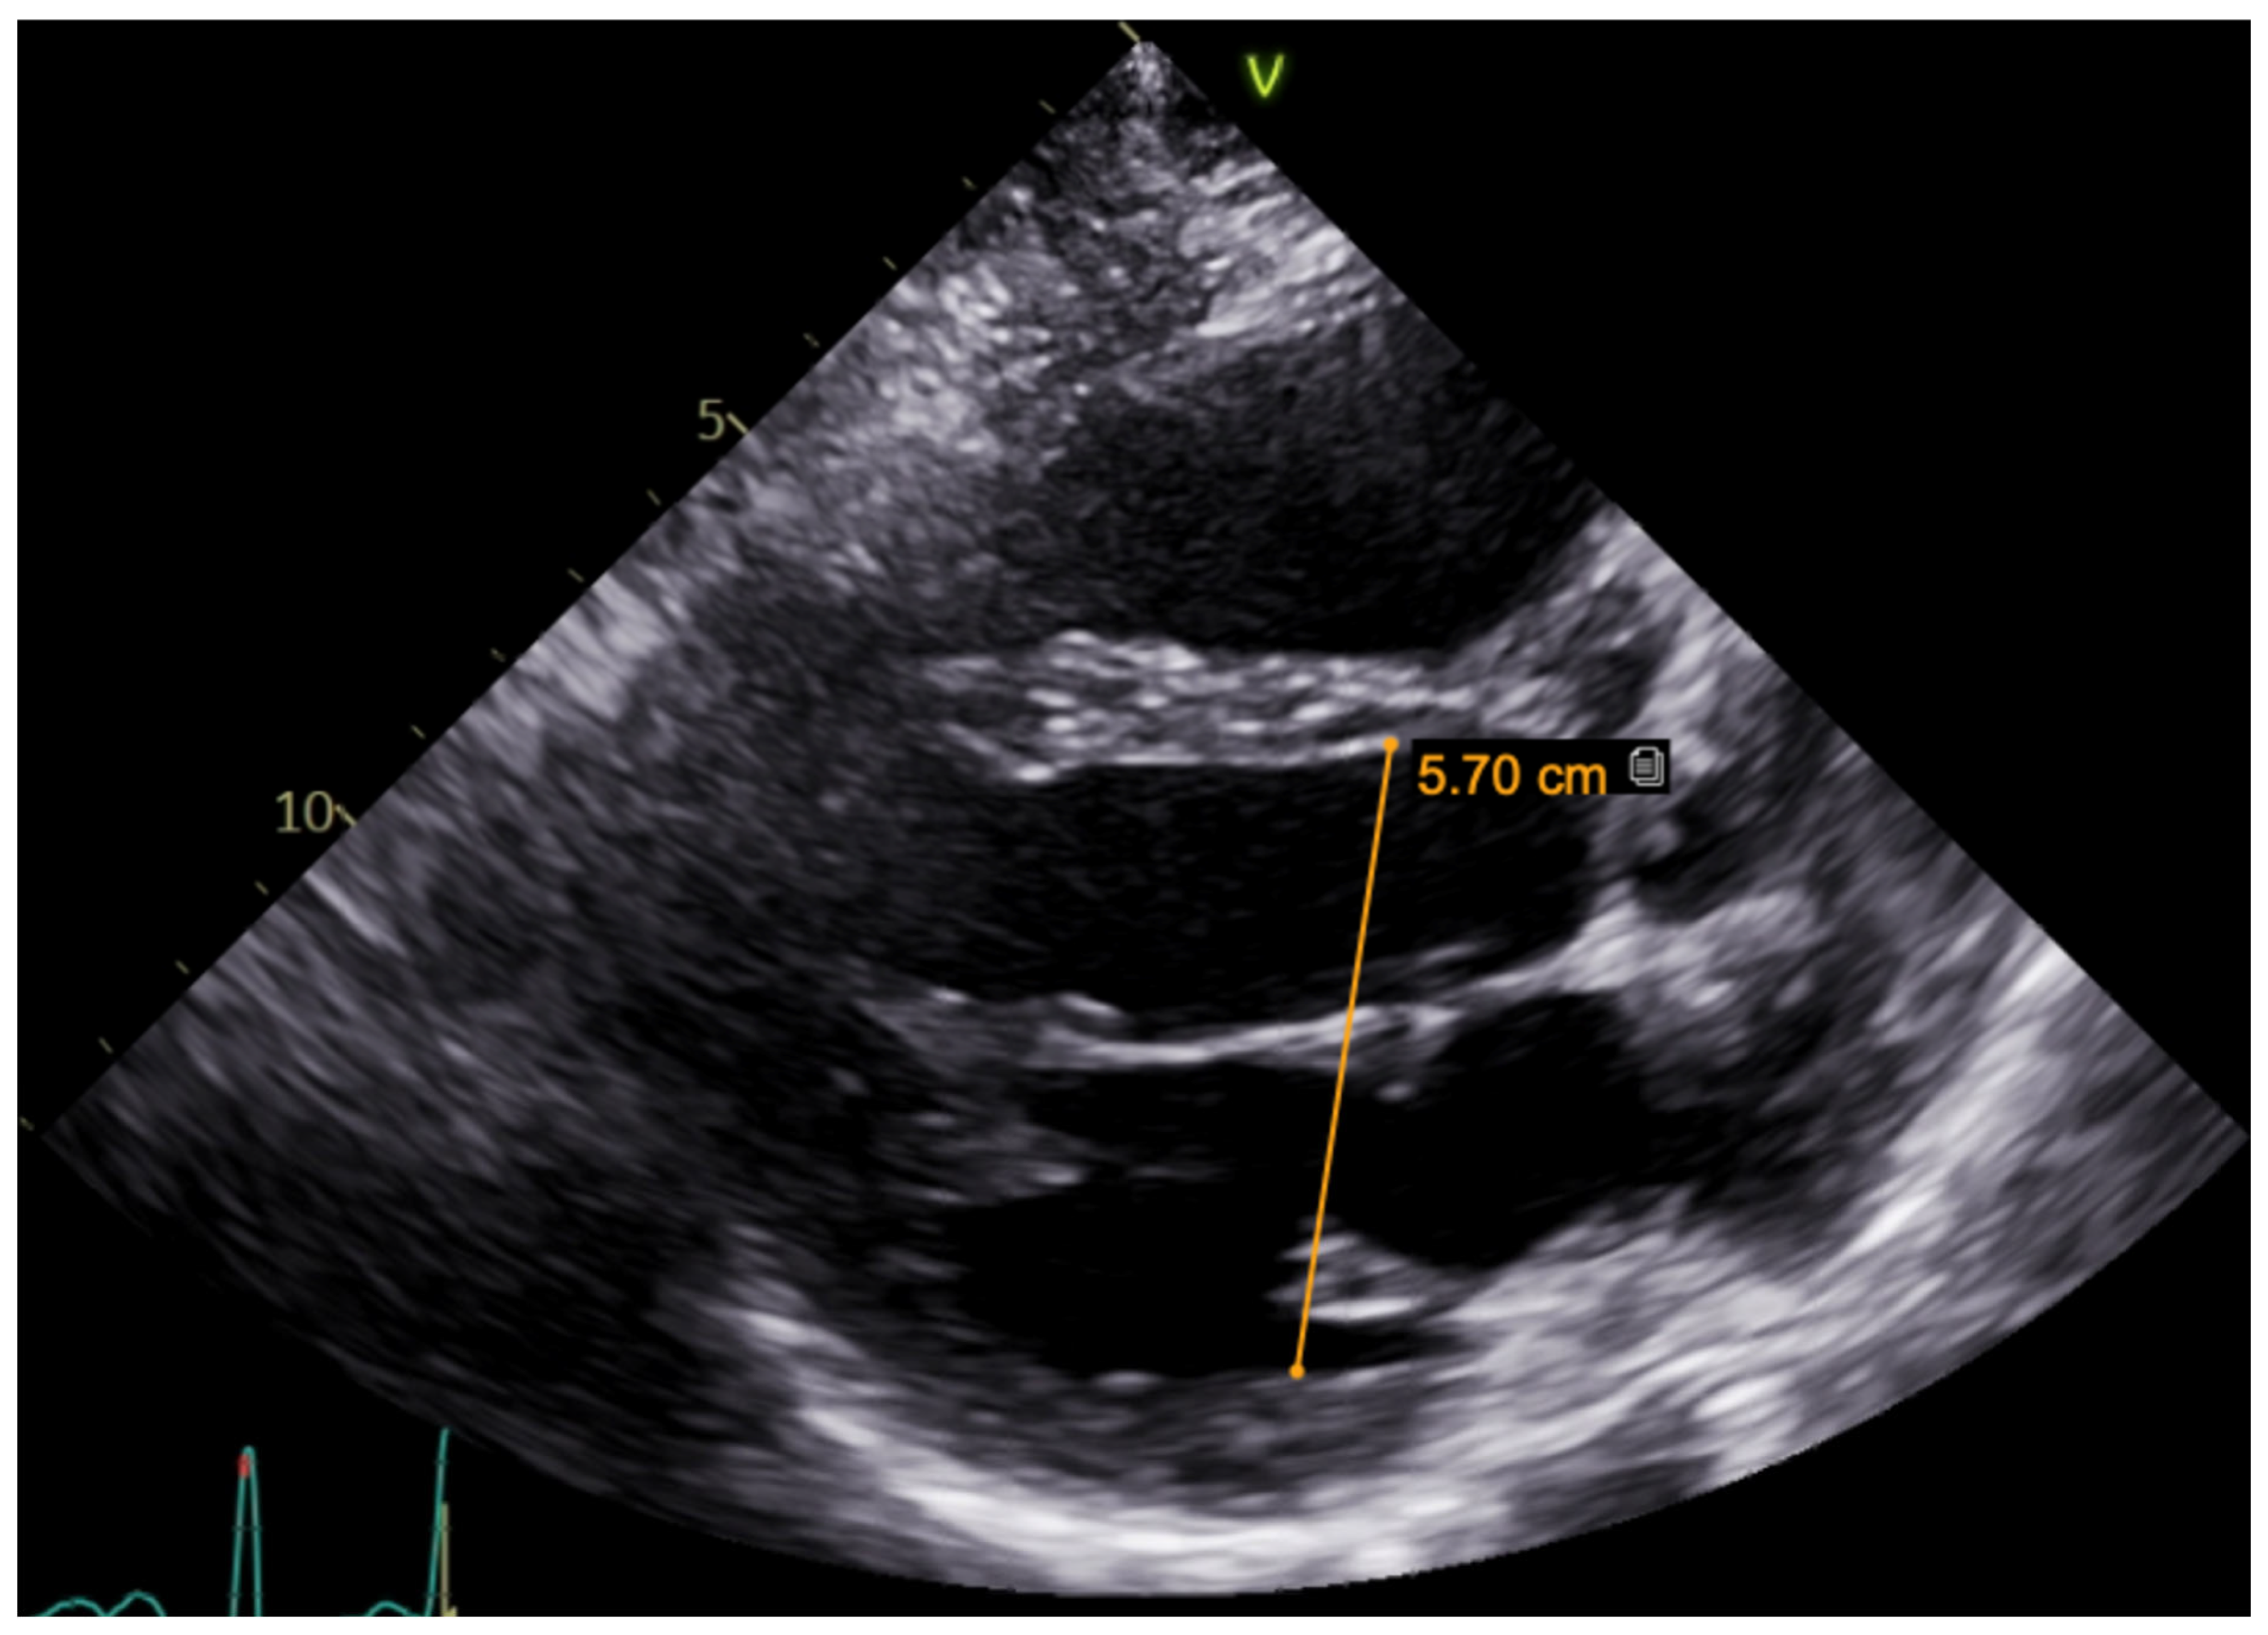

A hereditary disease was suspected, as the patient’s father died suddenly at the age of 40. Thus, targeted exonic sequencing of the SCN5A gene was performed. The pathogenic variant of the SCN5A gene (NM_198056.2) c.2440C > T (p.(Arg814Trp); rs199473161) was identified in a heterozygous state. The variant was advised to be evaluated according to clinical phenotype. It was decided to specify structural changes with repeated cardiac magnetic resonance imaging, although this scan was uninformative due to artefacts of ICD leads. Thus, TTE was repeated. No significant LV dilation (LVdd 54 mm) or systolic dysfunction (LV EF Simpson Biblane > 55%) were visible. The ergometry bicycle test demonstrated PVCs provoked by exercise, with most of them being monomorphic. A computerized tomography (CT) coronary angiogram ruled out coronary artery pathology, as the measured Agatston score was zero. During this time, the patient was on amiodarone and beta blockers. At the age of 31, the patient developed thyrotoxicosis and amiodarone had to be discontinued. Due to aggravated PVC symptoms, metoprolol was changed to 10 mg of bisoprolol per day. However, despite an optimized dose of beta blockers, the burden of PVCs increased, and approximately 66,491 (44%) PVCs were registered during 24 h Holter monitoring. TTE revealed a moderately dilated left ventricle (LVdd 57 mm, Figure 3) and impaired systolic function (LV EF 44%) in the context of ventricular bigeminy. A shared consultation with experts from the European Reference network of Rare Diseases was arranged, and a diagnosis of MEPPC syndrome was determined. Flecainide at a dose of 100 mg BID was added to bisoprolol at a dose of 10 mg. After several days, the dose of flecainide was increased to 300 mg a day, but no significant improvement in the patient’s status was observed. Thus, mexiletine was added, with the dose gradually titrated up to 150 mg three times a day. A substantial effect was seen in telemetry and registered in the ECG (Figure 4). All mentioned treatment adjustments were made during hospitalization in the arrhythmias department of Santaros Clinics, under telemetry surveillance, and with continuous monitoring of the patient’s clinical status. The patient was discharged with medical therapy of 7.5 mg of bisoprolol, 300 mg of flecainide, and 450 mg of mexiletine per day. During a follow-up visit after 1 month, a significant reduction in symptoms (fewer palpitations and better physical exercise tolerance), an improvement in LV function (LV EF by Simpson Biplane in repeated TTE was 53% and LVdd was 53 mm, Figure 5), and only 5819 (5%) PVCs under 24 h monitoring were observed. After 3 months, a further reduction to 858 (1%) PVCs under 24 h monitoring was registered and the patient had no complaints of palpitations. Dosages of antiarrhythmic drugs were reduced and as remission remained, discontinuation of mexiletine is under consideration.

Figure 5. TTE parasternal long-axis view after combination treatment (improvement in LV function, LVdd 53 mm).